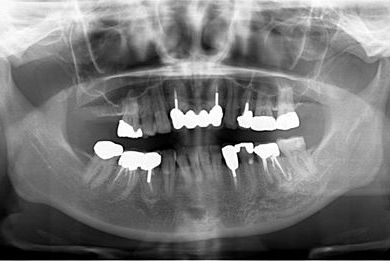

治療前

• 治療前